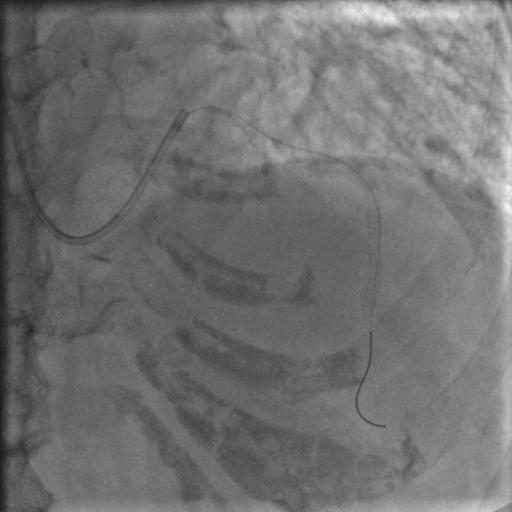

按照常规,更换指引导管,送入导丝,顺利通过闭塞病变到达前降支远端,很顺利,D-to-B时间70分钟,达标,曙光在前头。

图5

导丝过了之后常规造个影:

图6

没通,这个也很正常,急性冠脉闭塞导丝过了之后血栓还堵着是很经常的事,按常规打点欣维宁,考虑到她86岁,打入8ml欣维宁,造影: